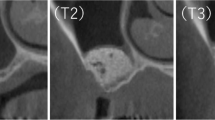

00 M observation—analyses of texture just after surgery revealed that taking into account entropy value, collagen-CP and CP materials was similar to reference bone tissue. The DifEntr feature also shows that CP was closer to the bone structure. 03 M observation—after 3 months from surgery, the CP material becomes more similar to bone structure taking into account Entr., DifEntr. and LngREmph. Entropy shows that all materials were under a rebuilding process. 06 M observation—after 6 months from surgery, the materials were still rebuilding. However, the CP microstructure was more similar to the reference bone tissue taking into account texture analyses. 09 M observation—after 9 months of observation period, the study shows that all materials were still rebuilding, but the CP material was similar to the bone one taking into account the two features (Entr and LngREmph). 12 M observation—the last period of observation revealed progressive healing process. All materials were similar to the bone. Nevertheless, the CP bone substitute had higher entropy contrary to collagen-CP and pure collagen, while its microarchitecture was most similar to the reference bone tissue without distinction to trabecular or cortical after 1 year of observation (Fig. 4a, b, c). Based on the texture analyses, it can be presumed that after a 12-month observation of the healing process, the microstructure of used CP material becomes compound cortical and trabecular tissue.

Texture analyses can be confirmed by radiographs from 3 groups of presented materials. It has been observed that materials after the 12-month period can be similar to the bone, but the healing process looks different every 3 months and for each material (Fig. 3). Our study proves that using collagen-CP material ensures bone tissue formation better than pure collagen. Nevertheless, the CP bone substitute material revealed a slightly better healing process contrary to Collagen-CP, and it can be caused due to its resorbability level. The mineral part of human bones consists of crystalline calcium phosphate, i.e. hydroxyapatite. Now, synthetic hydroxyapatite (CP) reveals osteoconductive and biocompatible properties. It is widely used in oral and orthopaedic surgery to fill bone defects thanks to its support proliferation properties. Nevertheless, its low bioresorbability effects remain after surgery for a long time [12, 19, 20]. Texture analyses have shown that Collagen-CP becomes similar to the reference bone just after few months of healing. The CP material is also considered, but we have to take into account its low level of bioresorbability and the need of longer period of observation of this material.